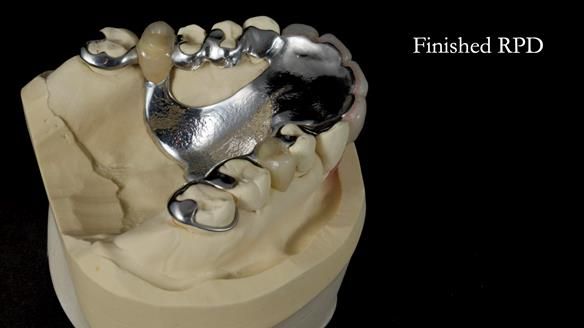

- Metalwork framework try-in – to verify fit, path of insertion, and support.

This is one of those cases that reminds me why I love removable prosthodontics. Pam was an absolute joy to treat — we were on the same page throughout. Her old upper flexible denture was loose, uncomfortable, and unaesthetic. We replaced it with a carefully designed metal-based upper partial denture/splint and new porcelain-bonded-to-zirconia (PBZ) crowns for the canines. The result is stable, comfortable, and natural-looking.

- Diagnosis and plan – Flexible upper denture ill-fitting with poor stability, retention, and appearance. Plan: metal-based upper partial denture/splint with lighter porcelain-bonded-to-zirconia crowns on UR3 and UL3.